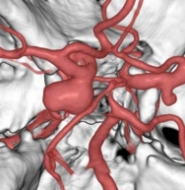

治療前

物が二重に見えるようになって発症した内頚動脈大型動脈瘤(矢印)の症例です。クリッピング術で直接動脈瘤をつぶすことができないため、バイパス術(矢印)を増設し内頚動脈を遮断することで動脈瘤を治療しました。